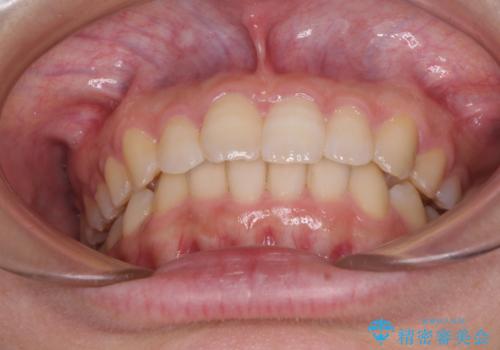

最難関と思われたシザーズバイトは比較的短期間で解消されました。

しかし、治療中に2度の出産を経験され、治療期間は長くなってしまいましたが、咬みやすく、清掃しやすい歯列を獲得することができました。